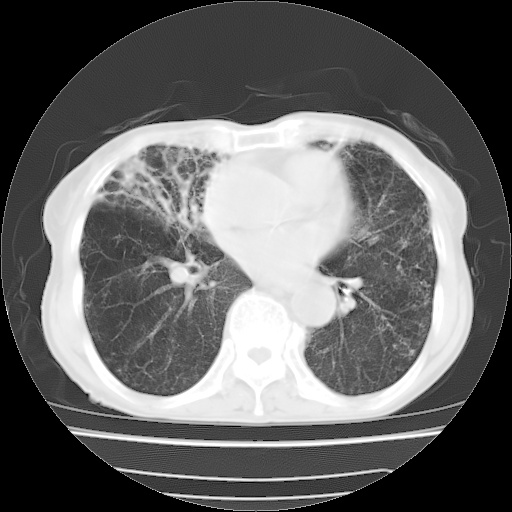

病人发热、气促就诊。原二周前已行ct扫描,当时诊断为双肺下叶、右肺中叶支气管扩张并感染,双肺上叶片状渗出性病变。今天复查胸部ct,双肺下叶支气管扩张并感染病灶较前明显吸收,但双肺上叶渗出性病变较范围较前明显增大。

现传今天ct图像给大家讨论。

双肺多发大片状、斑片状高密度渗出影,部分实变,考虑病毒性肺炎。